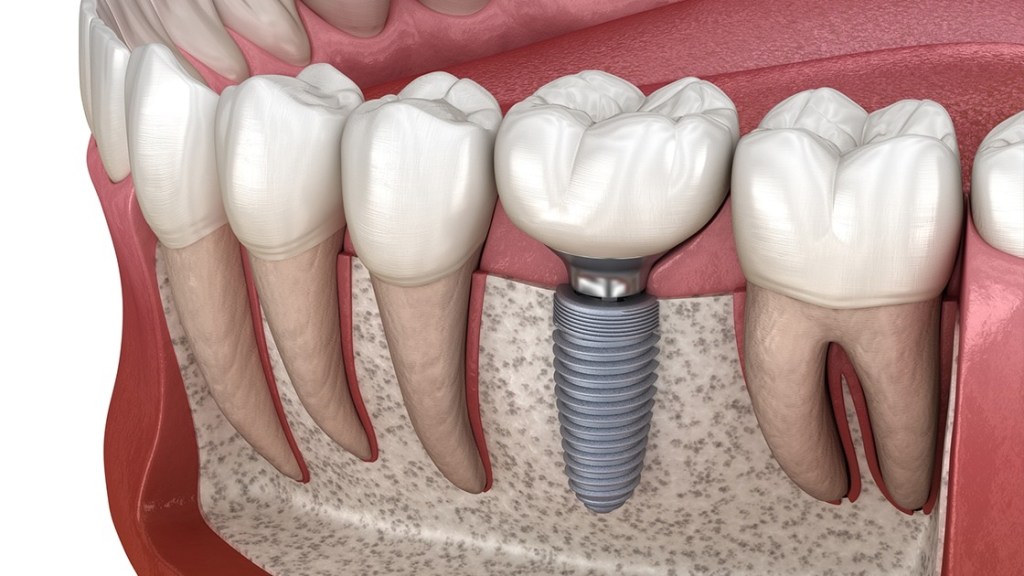

① 植牙與自然牙的「牙齦形狀不同」

自然牙的牙冠與牙齦之間,有一個「天然的牙齦弧度」,像是一個小小的穩固坡度,可以幫忙阻擋食物。

但植牙是:

• 植體(螺絲)

• 基台

• 假牙牙冠

三個部分組成,銜接位置比較「直、光滑」,沒有自然牙那種天生的弧度。

👉 所以食物會比較容易卡在牙齦邊緣。